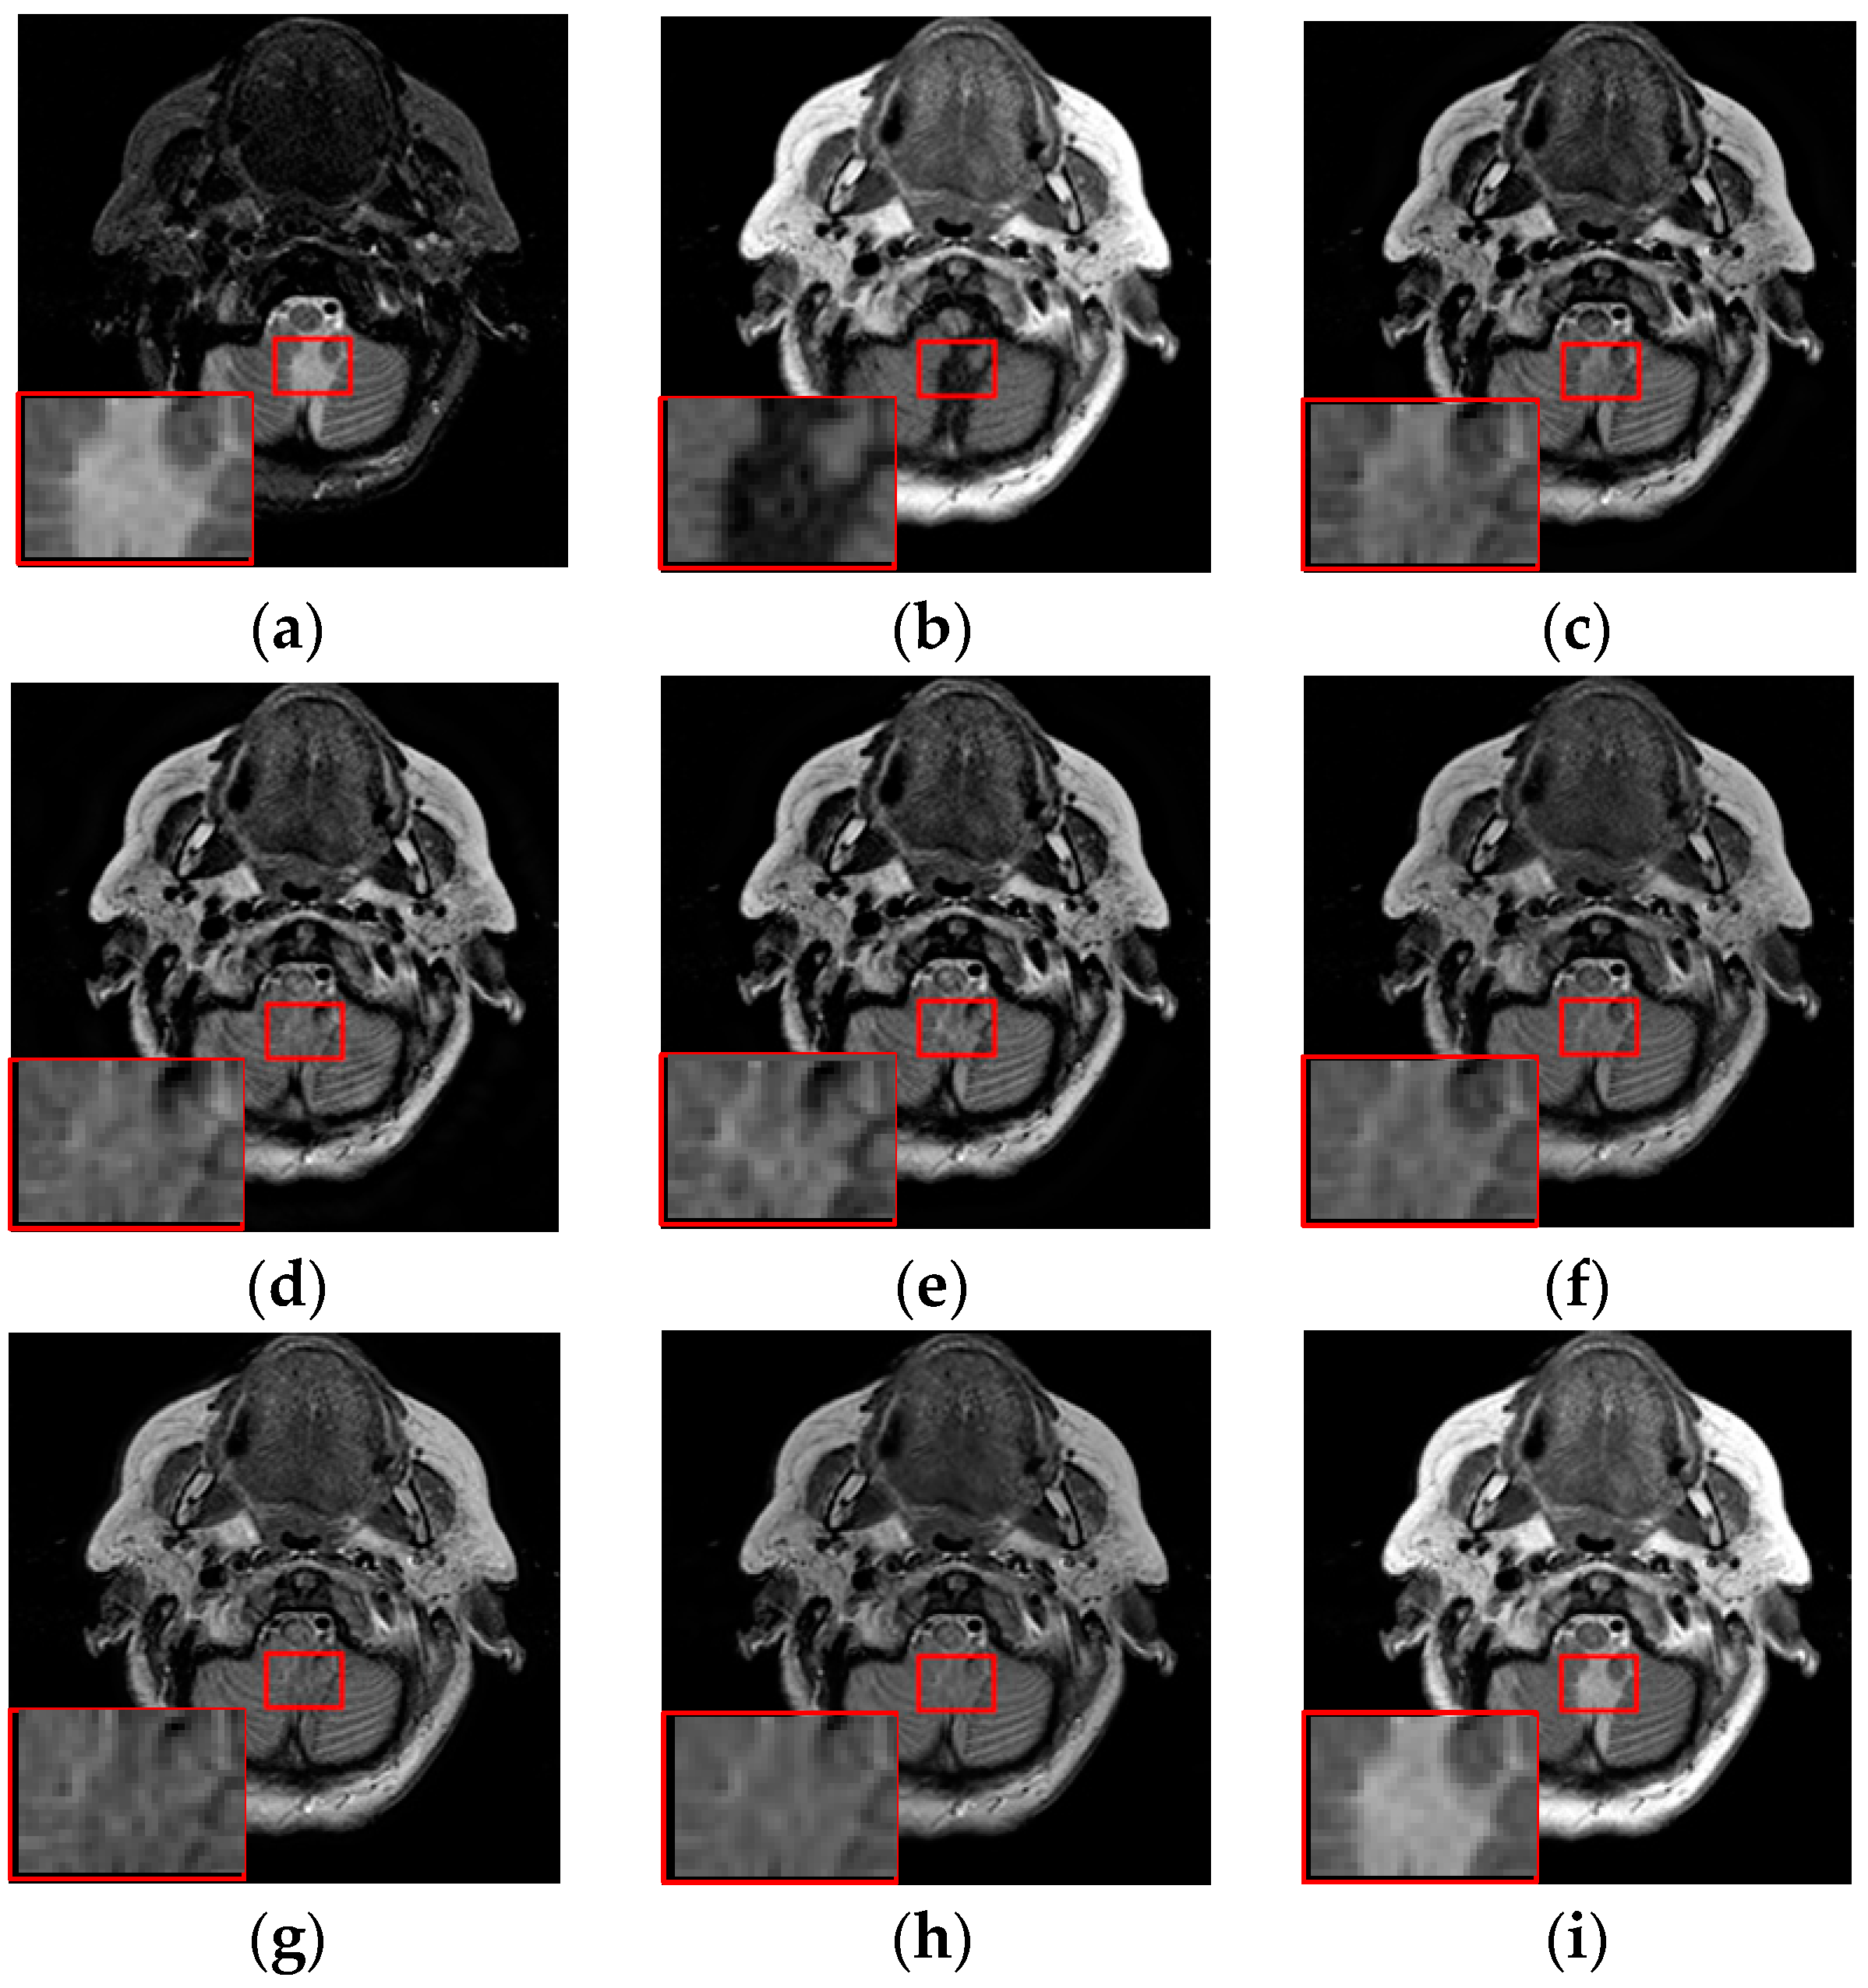

The fusion results of different methods about “MR-T1/MR-T2” (see Figure 8a,b) are shown in Figure 8c–i. For this experiment, the detail information (shape, edge, texture et. al) in the red rectangle is mainly from the MR-T1 image while the energy information (brightness, contrast et.al) mainly from MR-T2 image. Among these fusion results, it can be seen that the details of the fusion results produced by the DTCWT, Curvelet and NSCT methods are severely damaged, especially the Curvelet method. Although the Liu-ASR, Kim and Zhu methods can relatively effectively protect the edge details of the source image, they do not protect the contrast of the image well. This is very disadvantageous for medical images with high-quality requirements, and is not conducive to subsequent medical image processing and recognition tasks.

Figure 8.

Fused results of MR-T1/MR-T2 medical images by different methods. (a) MR-T1; (b) MR-T2; (c) DCTWT; (d) Curvelet; (e) NSCT; (f) Liu-ASR; (g) Kim; (h) Zhu; (i) Proposed.

By comparison, our fusion result (Figure 8i) can not only effectively protect the edge detail information of the source image, but also maintain the contrast of the source image, which is mainly due to the detail enhancement processing of training set and the clustering techniques to classify brightness and detail groups before dictionary learning. At the same time, little artificial false information is introduced in our fusion result, which means that the visual effect of the proposed method outperforms others methods in this experiment.